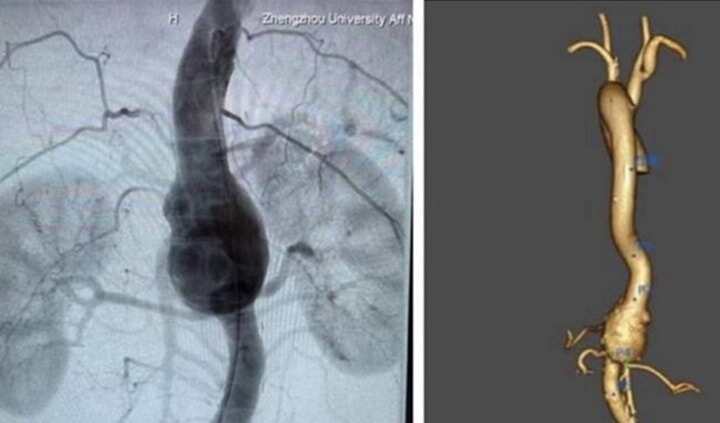

“3D打印”技術助力治療高難度主動脈瘤

2022112日,鄭大一附院大血管外科宋燕團隊應用3D打印技術成功完成兩例高難度主動脈手術,術后患者恢復順利。一位50歲的男性患者,以“腹痛1月余”為主訴入院,外院CTA提示:腹主動脈瘤樣擴張,累及腹腔干動脈、腸系膜上動脈和雙腎動脈。